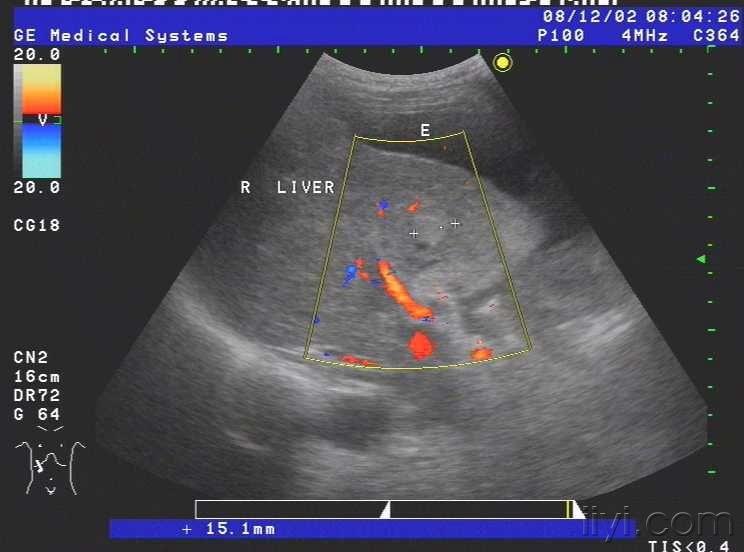

患者女,69岁,病毒性肝炎病史三年余,近半月自觉腹部胀满,来我院就诊,超声查示肝脏被膜不光滑,呈锯齿样,肝内回声不均匀,肝内多发小中等偏强回声团块,大小约1.5cm-3.0cm不等,无明显包膜,境界较清,另于肝右前叶近肝表面见一个大小约4.5cmx2.4cm的椭圆形实性低回声团块,至此处被膜略隆起,团块无明显包膜,伴侧方声影,后方回声增强,内部回声均匀,CDFI未见血流信号.右叶内另见两个类圆形囊性无回声区,肝内管道结构显示不清,肝门脉主干内径约1.1cm.胆囊壁厚1.0cm,囊内透声尚可,脾脏轻度增大,脾门脉无扩张;平卧位腹腔扫查于肝上前间隙肝肾隐窝脾肾隐窝双髂窝均见液性暗区.超声提示:1.肝硬化肝内多发实性团块合并胆囊炎脾轻大及大量腹水;考虑不除外肝癌?